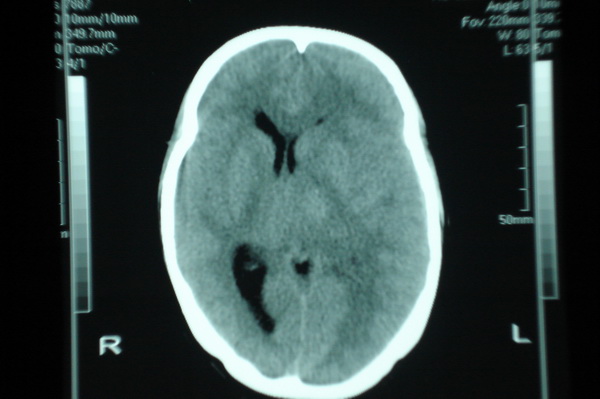

标题: CT11943:男,25,头痛伴癫痫发作数年.请会诊. [打印本页]

男,25,头痛伴癫痫发作数年.

左侧脑室局部受压闭塞,相应脑实质有等密度病变,顶叶区见均匀低密度病灶,外围见钙化有占位效应,胶质瘤可能,血管畸形不排除,建议强化或磁共振